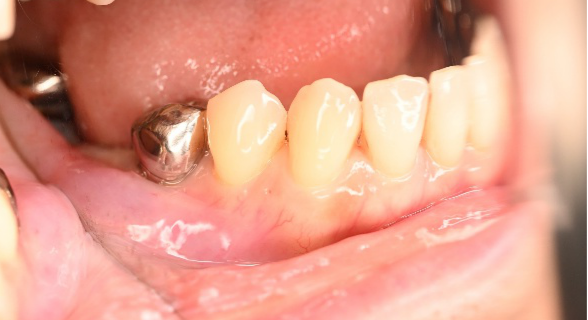

男性 Kさん 60代 (インプラント)

主訴

下の左右歯がないところに歯を入れたい。

治療内容

左右それぞれ3本歯がないところに2本ずつインプラントを埋入しました。

所感

上と下の歯の咬合接触がないすれ違い咬合です。上下義歯で対応するには最も難しいタイプの欠損状況です。治療開始前は、上下部分入れ歯が入っていましたが、入れ歯の安定が悪く、あちこちの歯茎に入れ歯が当たって痛く、満足に噛める状態ではありませんでした。上顎は、残ってる歯を活用するマグネット式総義歯を、下顎はインプラントを提案しました。上顎は、現在残っている歯の根管治療中です。上顎にマグネット式総義歯がはいれば、何でも食べられるようになります。

インプラント4本:¥363,000×4本=¥1,452,000(税込)

ポンティック2本:¥115,500×2本=¥231,000(税込)

合計:¥1,683,000(税込)

Before

▼初診時に使用していた部分入れ歯を装着したところ

▼インプラント埋入前

After

▼インプラント埋入後